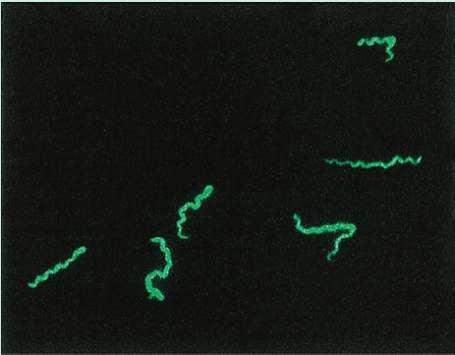

为了确认潜在的献血者是否真的患有梅毒,该血清被用于特定的免疫荧光测试。如果这个结果也是阳性的,就证实这位捐赠者确实患有梅毒,她的血液不能用于输血,她还会被转介治疗梅毒。

梅毒的特异性血清学检测

梅毒螺旋体引起梅毒。这种细菌是一种柔韧的螺旋杆(Fig 5.10)。为了获得如图所示的图像,进行了荧光梅毒抗体吸收试验(FTA-ABS)。试验血清首先被非致病性梅毒螺旋体吸收,以去除交叉反应抗体。然后,将吸收的试验血清与梅毒螺旋体在显微镜载玻片上反应,根据Fig 5.6中描述的间接免疫荧光法,在荧光显微镜下用异硫氰酸荧光素(FITC)偶联的抗人免疫球蛋白G(IgG)抗体检测任何与梅毒螺旋体结合的抗体。

Fig 5.10 荧光梅毒螺旋体抗体吸收试验可见梅毒螺旋体